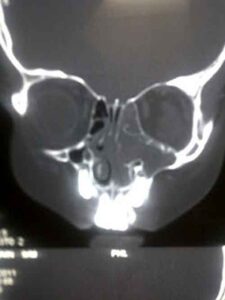

Una nuova tecnica laser per fermare la forte lacrimazione che colpisce i pazienti affetti dall'ostruzione del dotto o del sacco...

Trenta minuti in ospedale come tre giorni al mare. E' possibile da oggi presso il reparto di Otorinolaringoiatria del Policlinico...